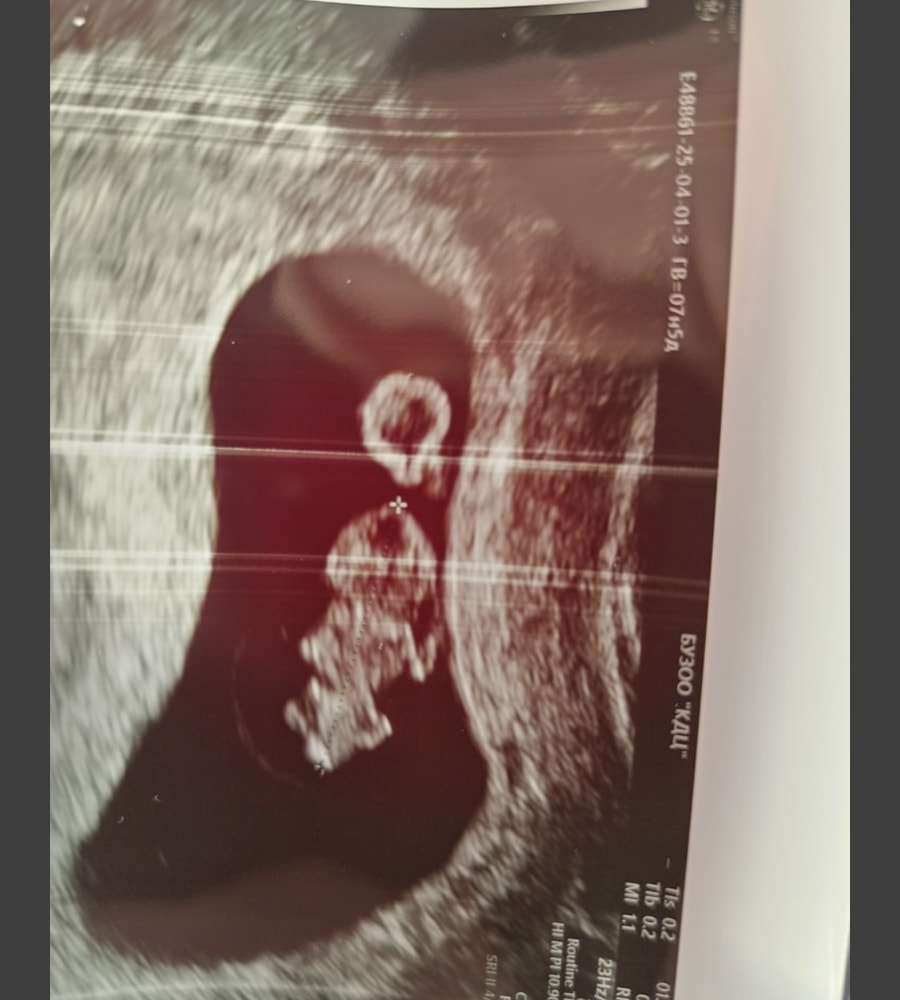

УЗИ, КТГ, доплерДевочки, может кто сталкивался. Сходила на узи. Срок 7,5нед. КТР 14, СБ 160. Узист ничего плохого не сказала, кроме тонуса. Еду домой, читаю заключение. Желточный мешочек 6,7 мм. Естественно в интернете ничего хорошего это не значит. Написала доктору. Она сказала главное сб есть и ктр растет. На душе все равно тяжко. Но логически, это значит жм почти половина эмбриона. А на узи жм не большой😭

Лёвушка, спасибо 🙏 предыдущее узи было перед выпиской в пятницу. Сегодня побежала потому что начала просто паниковать из-за внезапного отсутствия тошноты. В пятницу жм 4, ктр 11